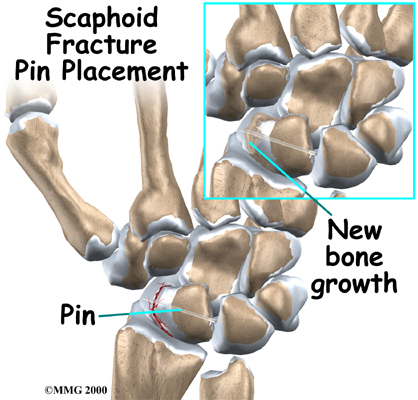

Bone Graft Method

Your surgeon may use a bone graft. A bone graft involves taking bone tissue from another spot in your wrist and inserting it into the fracture. A bone graft can stimulate healing on the surface of the bones. The bone graft is usually taken through a second small incision just above the wrist. (It is sometimes taken from the pelvis, through an incision in the side of your hip.)

After the bone graft is placed between the parts of the scaphoid bone, some surgeons also insert a metal pin or screw across the bone. The goal is to hold the two pieces of bone tightly together, allowing them to fuse into one bone.

When the surgery is complete, the incision is stitched closed. The arm is placed in a large bandage or a splint. You are then awakened and taken to the recovery room.

Sometimes the bones still do not heal as planned. Surgeons call a fused bone that fails to heal a pseudarthrosis. If the nonunion continues to cause pain, you may need a second operation. Your surgeon will probably add more bone graft and check that the pins or screws are holding the bones together.